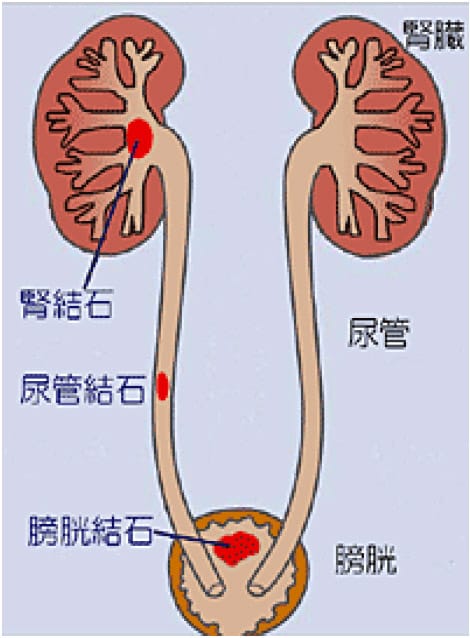

結石破砕治療の実際 – Radiology@Home。尿路結石の治療について | 医療法人社団實理会 東京国際大堀病院。尿路結石外来|尼崎市 おかだ腎泌尿器・ペインクリニック| 阪神。ぷっち おまとめ2袋 白米10キロ。尿路結石症(腎結石・尿管結石)の治療法 - 船橋クリニック 千葉。体外衝撃波結石破砕装置(ESWL)|焼津市立総合病院。尿路結石の検査 - 船橋クリニック 千葉県泌尿器科 尿路結石症。痛みを乗り越えた者だけが手にする秘宝商品説明これは単なる石ではありません。長きにわたり忍耐と痛みを経験した末、身体から生まれた奇跡の結晶です。賢者の石と呼ばれるにふさわしい、神秘的な輝きを放つ逸品!その力強い存在感は、あなたのコレクションに一層の深みを与えることでしょう。おすすめポイント•世界に一つだけのオリジナル品!•痛みを耐え抜いた歴史を感じられるストーリー付き•お守りやアクセサリーの材料にも最適こんな方におすすめ!•面白グッズ好きな方•他人とは違うコレクションを目指す方•人生の痛みを乗り越える象徴が欲しい方これを手にすることで、あなたも「賢者」の仲間入りを果たせるかも?一点限りの出品ですので、お見逃しなく!。尿管結石の最新治療技術 - Genspark。尿路結石症 – 社会医療法人 北腎会 坂泌尿器科千歳クリニック。尿管結石の最新治療技術 - Genspark。巨大腎結石への挑戦 | 研究報告 | 医療法人社団實理会 東京国際。尿路結石(尿管結石、腎臓結石、膀胱結石)の原因や治療について。尿路結石」について|市立貝塚病院